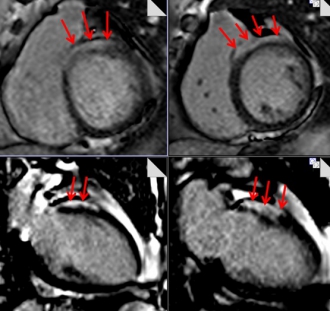

心サルコイドーシスの症例。心基部の中隔に遅延造影を認める(矢印)